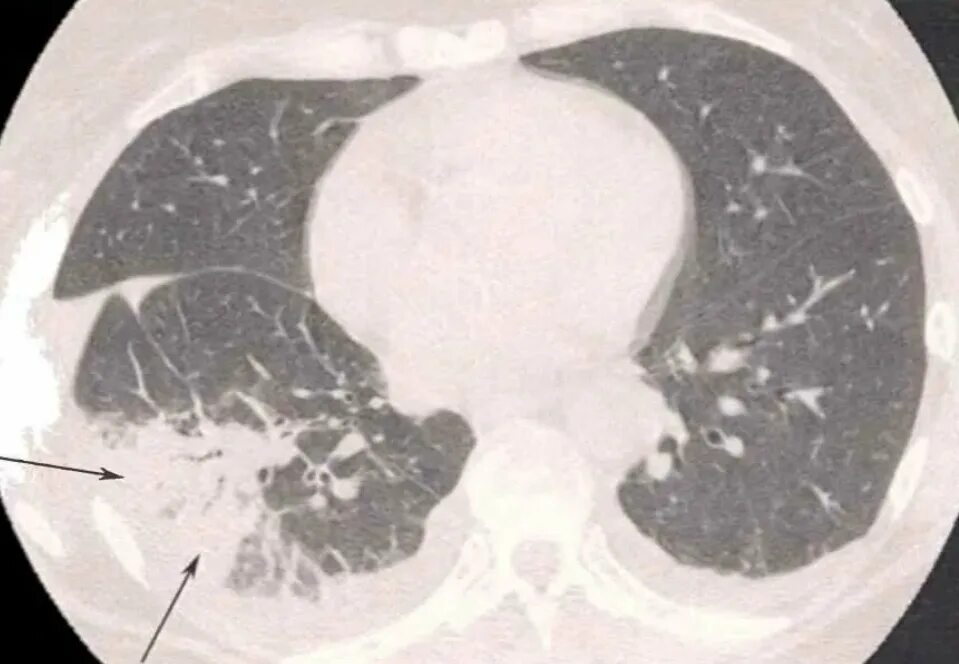

Как выглядит пневмония на кт